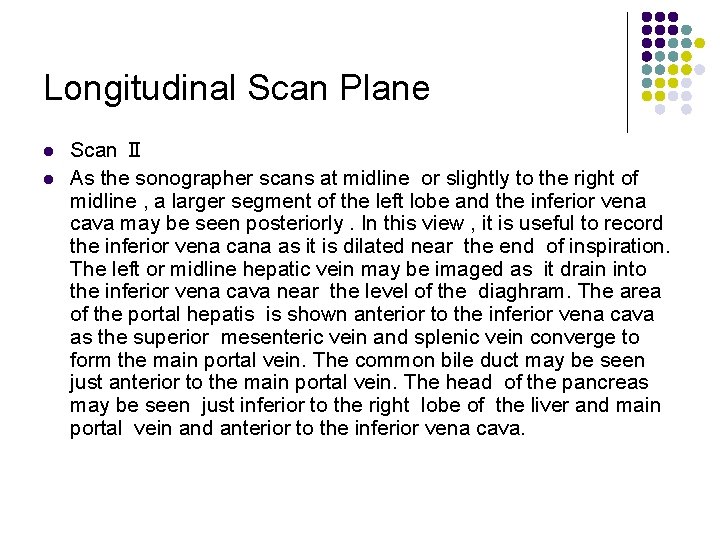

Longitudinal Scan Plane l l Scan Ⅱ As the sonographer scans at midline or slightly to the right of midline , a larger segment of the left lobe and the inferior vena cava may be seen posteriorly. In this view , it is useful to record the inferior vena cana as it is dilated near the end of inspiration. The left or midline hepatic vein may be imaged as it drain into the inferior vena cava near the level of the diaghram. The area of the portal hepatis is shown anterior to the inferior vena cava as the superior mesenteric vein and splenic vein converge to form the main portal vein. The common bile duct may be seen just anterior to the main portal vein. The head of the pancreas may be seen just inferior to the right lobe of the liver and main portal vein and anterior to the inferior vena cava.